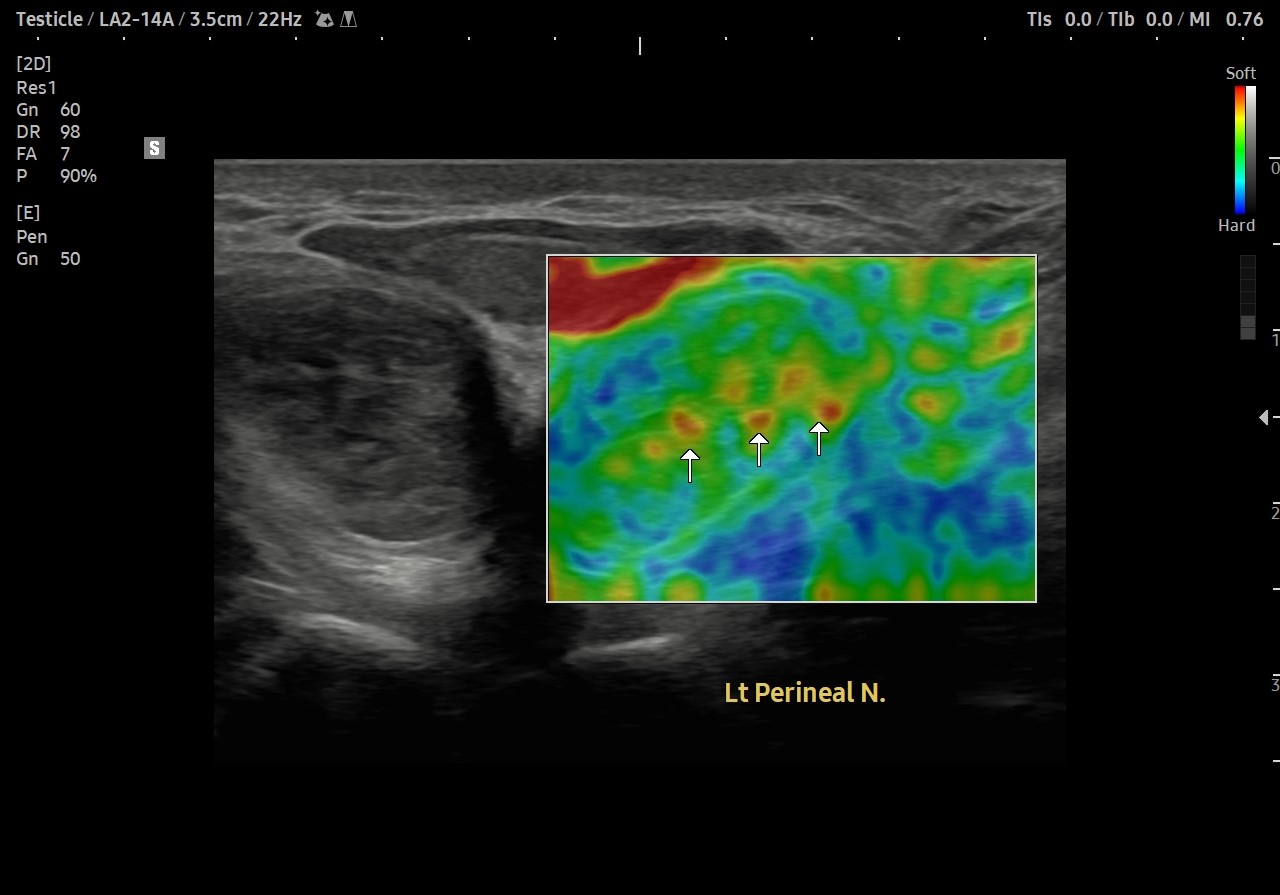

[치료 전]

[치료 후]

- 치료횟수 : 30 회